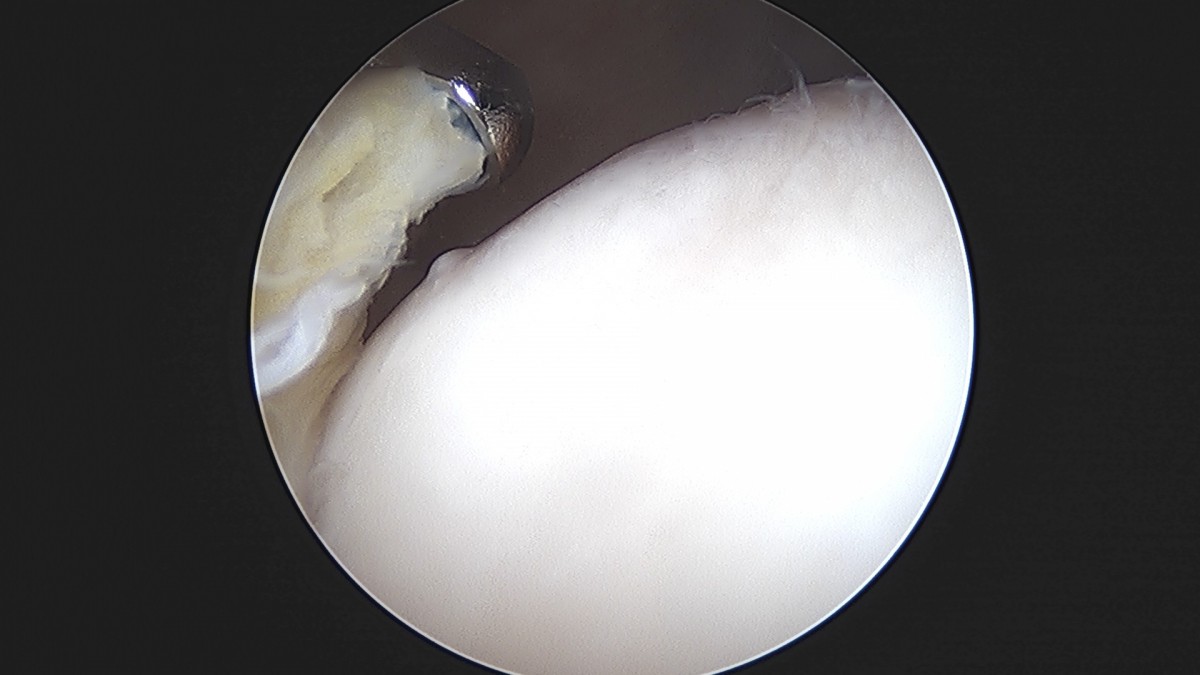

이재상원장님 무릎 반월상 연골판 절제술 최용O 환자

작성자 최고관리자 댓글 0건 조회 379회 작성일 25-09-16 15:57